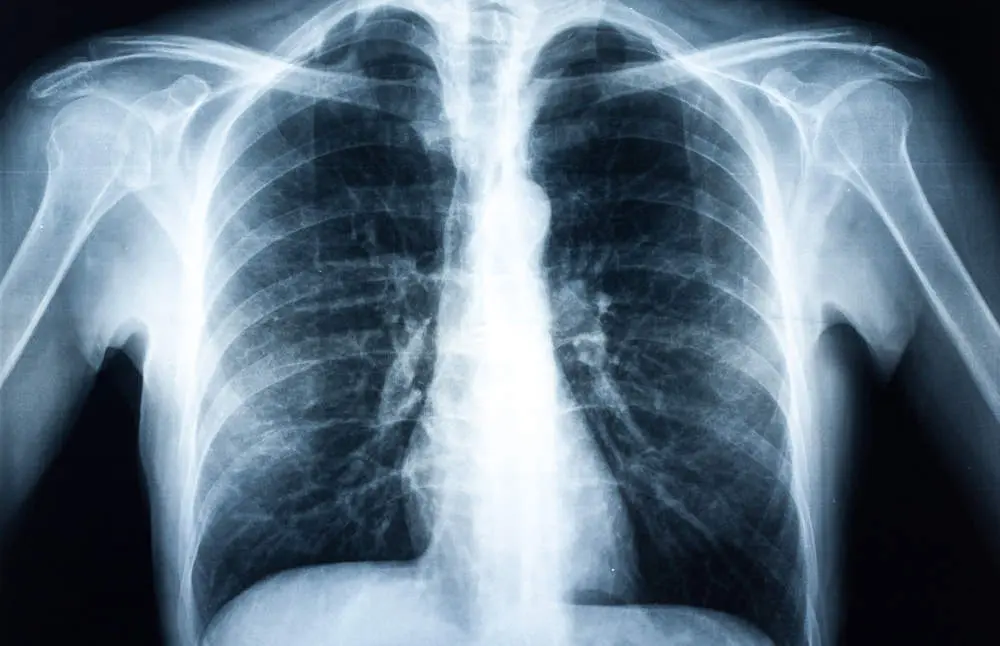

Xray of a human torax isolated

En concreto KeyZell han desarrollado un sistema de Inteligencia Artificial para el diagnóstico de cáncer por imagen. Se trata de una herramienta innovadora que permite mejorar la precisión del diagnóstico de cáncer por imagen a través de una radiografía o una tomografía por emisiones de positrones conocido como PET y las normas DICOM. El dispositivo ha sido entrenado con un total de 108.948 imágenes de rayos x de tórax correspondientes a 32.717 pacientes. El tiempo de procesado por radiografía es inferior a 1 minuto y permite la generación de colas de trabajo de manera simultánea por múltiples usuarios.

Esta herramienta de Medicina de Precisión es capaz ya de facilitar a los radiólogos detectar si un paciente posee masa tumoral con una precisión del 92% y ofrecer el diagnostico al radiólogo en menos de 1 minuto. El prototipo ha sido entrenado para cáncer de pulmón y cáncer de mama. Además ha sido validado por un comité ético.